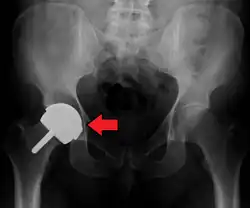

Dislocation

Dislocation (the ball coming out of the socket) is one of the most common complications. Hip prosthesis dislocation mostly occurs in the first three months after insertion, mainly because of incomplete scar formation and relaxed soft tissues.[15] The chance of this is diminished if less tissue is cut, if the cut tissue is repaired and if large diameter head balls are used.[17] Surgeons who perform more operations tend to have fewer dislocations. Important factors which are related to dislocation are: component positioning, preservation of the gluteal muscles and restoration of leg length and femoral offset.[18] Keeping the leg out of certain positions during the first few months after surgery further reduces risk.

The direction of the acetabular cup influences the range of motion of the leg, and also affects the risk of dislocation.[16] For this purpose, the acetabular inclination and the acetabular anteversion are measurements of cup angulation in the coronal plane and the sagittal plane, respectively.